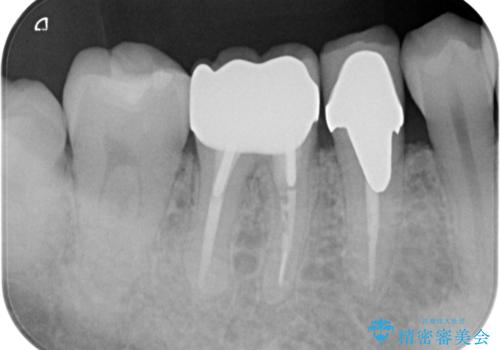

- 右下6 仮歯+ジルコニアクラウン 11,000円+121,000円費用は治療当時の料金となります

気になっていた銀歯を自然な色に変えることができ、大変喜んでいただけました。